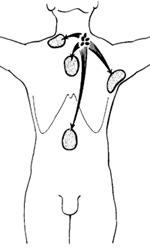

Lymphangiography swept away earlier misconceptions concerning the unpredictable, capricious distribution of lymph node involvement in patients with Hodgkin's disease and made possible systematic attempts to map sites of disease, Rosenberg and Kaplan (1966), in a study of lOO consecutive, previously untreated patients with Hodgkin's disease, found that involvement of various chains of lymph nodes was distinctly nonrandom; when a given chain of lymph nodes was affected, other chains known to be directly connected with it via lymphatic channels were likely also to be involved, either concurrently or at the time of first relapse, Even extralymphatic sites such as the lung, liver, and bone marrow were more likely to be involved in association with certain predictable patterns of lymph node and/or spleen involvement. These studies were subsequently extended (Kaplan 1970, 1980) to overlapping series of 340 and 426 consecutive previously untreated cases, with results which strongly confirmed and reinforced the initial conclusions. Similar analyses have been presented by other groups of investigators (Banfi et al. 1969; Han and Stutzman 1967), again with generally similar conclusions. Two distinctivcly liifferent theories, the '.contiguity" theory of Rosenberg and Kaplan ( 1966) and the "susceptibility'. theory of Smithers ( 1970, 1973), have been proposed to account for the patterns of spread observed in Hodgkin's disease. The contiguity theory postulates that Hodgkin's disease is a monoclonal neoplasm of unifocal origin which spreads secondarily by metastasis of pre-existing tumor cells, much like other neoplasms, except that the spread is predominantly via lymphatic rather than blood vascular channels. The term contiguity refers to the existence of direct connections between pairs of lymph node chains by way of lymphatic channels which do not have to pass through and be filtered by intervening lymph node or other lymphatic tissue barriers. Smithers (1973) suggested that the giant cells of Hodgkin's disease may move in and out of lymph nodes from the blood stream, following a traffic pattern similar to that known to occur with normallymphocytes. Emphasis was placed on the concept that Hodgkin's disease is a systemic disorder of the entire lymphatic system. Thus, the possibility was suggested that the disease may have a multi focal origin, perhaps by spread of a causative agent with de novo reinduction in different sites rather than the spread of pre-existing tumor cells. After an initial site had become involved, the theory predicted that each of the remaining lymph node chains would have an independent probability of next becoming involved which was assumed to be proportional to the probabilities of initial involvement of the corresponding lymph node chains in patients with Stage I disease. Careful mapping of the initial sites of involvement in consecutive, previously untreated patients revealed the occurrence of noncontiguous patterns in only 4 (2%) of 185 patients with Stage 11 disease (Kaplan 1970). Hutchison ( 1972) compared the observed distributions in 158 of our Rye Stage 11 cases whose calculated frequencies were based on the random association of two or more sites with the probabilities given by their respective frequencies in 53 observed Stage 1 cases. The observed patterns for two or three involved sites departed significantly from random expectation. In particular, there was an apparent deficiency of bilateral cervical node involvement in the absence of associated mediastinal lymphadenopathy, an excess frequency of association between cervical and mediastinal node involvement, and a marked deficiency of all noncontiguous contralateral distributions. Lillicrap (1973) compared the predictions of the Smithers susceptibility hypothesis with the observed patterns of spread in three different series of patients with Hodgkin's disease. Bilateral cervical lymph node disease was observed significantly less often than predicted, whereas involvement of the neck and mediastinum was more frequent than predicted. There were 46 instances of homolaterai cervical-axillary involvement and only two contralateral cases, whereas equal numbers of each would have been predicted by susceptibility theory. Conversely, the observed patterns were consistent with the contiguity theory in all but 8 ( 4%) of 212 cases. Modifications of the susceptibility theory were subsequently proposed by Smithers et al. ( 1974) in an attempt to make the theory more consistent with observed distribution frequencies. These modifications, which accept the concept of spread via lymphatic channels, exhibit appreciably better agreement with observed patterns of two and three sites of involvement. The contiguity theory has also been tested with respect to the sites of first relapse in patients with regionally localized disease treated with limited field radiotherapy. Rosenberg and Kaplan (1966) found that 22 of 26 extensions of disease were to contiguous lymph node chains. Similar findings have been reported by others (Banfi et al. 1969; Han and Stutzman 1967). The most controversial issue is the association between involvement of the lower cervical-supraclavicular lymph nodes and the subsequent occurrence of relapse in the upper lumbar para-aortic nodes. Among 80 such cases at risk, Kaplan ( 1970) observed para-aortic node extensions in 29 (360/0 ). This was the single most prevalent site of extension in patients treated initially with local or limited field, supradiaphragmatic radiotherapy. Transdiaphragmatic extension was also the first manifestation of relapse in 33 ( 40% ) of 83 patients with clinical Stage land 11 disease studied by Rubin et al. (1974 ). Many para-aortic lymph node relapses occurred several years after initial treatment and frequently involved lymph nodes which were well visualized and appeared normal on the originallymphangiogram. It was suggested (Kaplan 1970; Rosen berg and Kaplan 1966) that spread in these instances had occurred in the retrograde direction

Fig. 4. Schematic diagram of postulated retrograde spread of Hodgkin's disease from low cervical-supraclavicular to para-aortie/celiac nodes via the thoracic duct and of contiguous spread to the mediastinal, ipsilateral axillary, and contralateral cervical-supraclavicular nodes, Reproduced, by permission, from the paper by Kaplan ( 1970)

from the supraclavicular fossa downward along the thoracic duct into the lumbar paraaortic nodes (Fig. 4) . The occasional presence of Reect-Sternberg and Hodgkin's giant cells in the thoracic duct lymph has been documcntect by Engeset et al. (1968). There is little dispute that these cells may enter the thoracic duct from involved lymph nodes below the diaphragm and travel upward to involve the cervical-supraclavicular lymph nodes. The possibility of retrograde spread from one peripheral lymph node chain to other, more distal chains by way of lymphatic channels lacking valves is also widely accepted. However, the concept of retrograde spread along the thoracic duct has been much more controversial because the duct is equipped with valves which should prevent retrograde flow. Yet, the pressure in the duct is only a few millimeters of water and reversal of flow was readily observed following chronic ligation of the thoracic duct in dogs (Neyazaki et al. 1965). Pressure gradients along the canine thoracic duct were often opposite to those required for antegrade flow (Browse et al. 1971 ). However, Dumant and Martelli ( I 973 ) were able to demonstrate radiopaque material in the para-aortic lymph nodes of only 1 of 16 dogs after ligation and cannulation of the thoracic duct and injection of opaque contrast material in the retrograde direction. Retrogradc flow might well occur more often in the thoracic duct of man, which is usually vertical, than in that of dogs, which is horizontal. Rouvicre ( 1932) noted that although the human thoracic duct usually has two competent valves at its upper end, a not infrequent normal variation involves the presence of a single incompetent valve, which is usually compensated by oblique insertion of the duct through the vein wall. Conceivably, prolonged compression and partial occlusion of the duct by enlarged lymph nodes near its insertion into the subclavian vein may cause dilatation of the duct with secondary valvular incompetence and reversal of flow. The role of vascular invasion (Rappaport and Strum 1970) in the spread of Hodgkin's discase is not fully understood. In a careful review of the original biopsy material in II patients with regionally localized Hodgkin's disease who developed extra nodal dissemination following primary radiotherapy, Lamoureux et al. (1973) failed to find evidence of vascular invasion. Kirschner et al. (1974) noted that vascular invasion was present in 7 ( 16% ) of 44 spleens involved by Hodgkin's disease and was associated with hepatic and bone marrow metastasis, early relapse, and decreased survival, whereas vascular invasion detected in 4 of 91 lymph node biopsies was not attended by an increased frequency of extranactal dissemination or a decreased survival rate. In a series of patients whose lymph node biopsies showed vascular invasion, Naeim et al. (1974) observed an average survival time of only 21.8 months, significantly less than the 65.8 month average survival of those patients in whom vascular invasion was not demonstrable in the original lymph node biopsies.